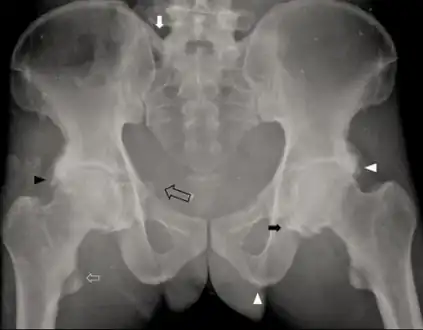

Individual with idiopathic hypoparathyroidism-diffuse osteosclerosis, capsular ossification around bilateral hip joints arrow, ossification of bilateral iliolumbar ligaments arrow, irregular bony excrescences arrowhead, subtle calcification of the right sacrospinous ligament open arrow